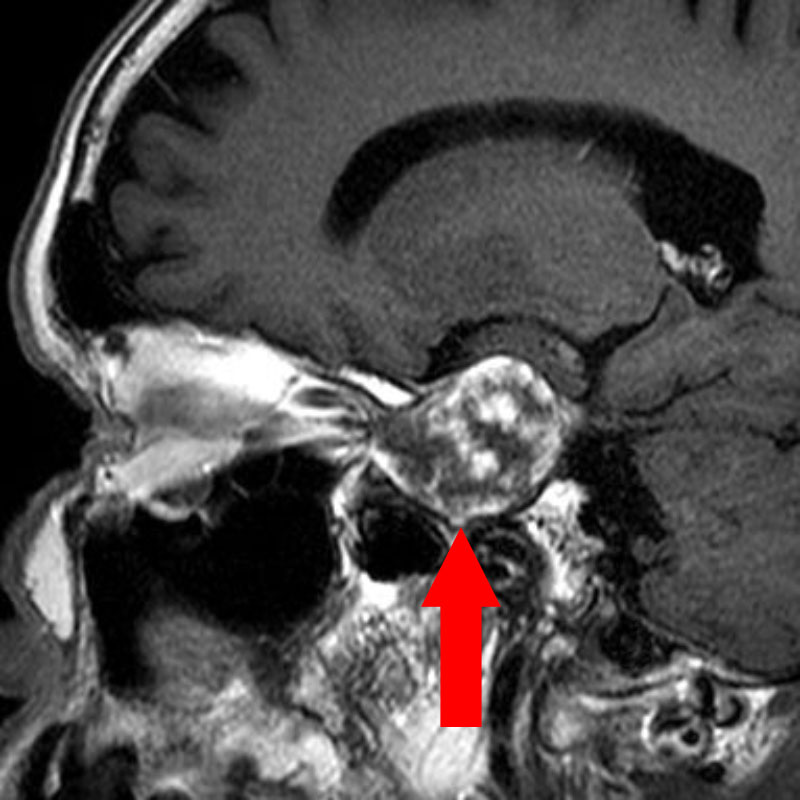

断層撮影

手術前1

手術前2